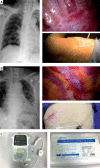

Photo 1

A – Placement of PVC by thoracoscopic guidance. The red arrow indicates the PVC. B – Placement of ICC by thoracoscopic guidance. The red arrow indicates the ICC. C – The electrical infusion pump (Apon) and catheter (Specath) PVC – paravertebral catheter, ICC – intercostal catheter.